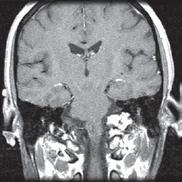

One of the many benefits of utilizing the MRF method as opposed to traditional MRI techniques is that it can be applied across vendors and machines to enable quantitative comparisons. “Before MRF, the shades of gray you received depended on all sorts of factors,” says Tom Griesler, MS, third year BME PhD candidate, whose research interests include MRF sequence design and optimization for brain and abdominal imaging. Results varied based on the series, settings, and manufacturer. Using MR Fingerprinting, numerical physical parameters enable comparison across time and space.

“We’re also developing something called quantitative T1rho mapping, an MRI-based measurement technique for contrast-free myocardial fibrosis detection,” says Sydney Kaplan, MS, 4th year BME PhD candidate. “This is part of my research where we’re trying to avoid administering gadolinium based contrast agents to patients who may have kidney disease. With standard scanning technology, we can’t see fibrosis on an MRI image. However, by using T1rho or an alternative method, Magnetization Transfer (MT), both of which are sensitive to macromolecules like collagen or proteins, we can see subtle changes in heart tissue.”

Going forward, MIITT may be venturing into deep learning to improve the resolution of multiple parameter maps and decrease scanning time. Its goals will continue to revolve around solving the challenges that radiologists have on a daily basis using MRI to diagnose disease. “We will continue to look for collaborators who have questions that we can seek to answer with MRI technology,” says Dr. Seiberlich.